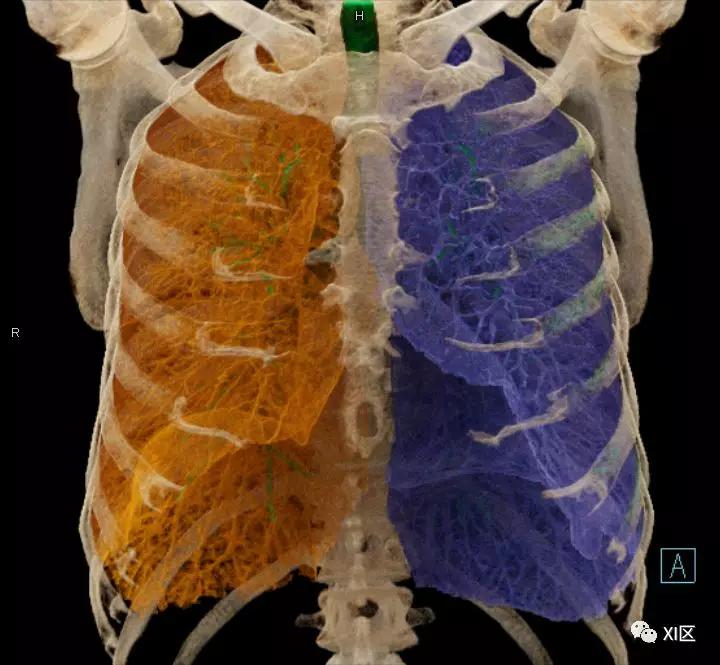

前后位,双侧位,后前位显示气道肺与胸部骨骼的关系

肺的分叶

左肺借斜裂成上、下两叶;右肺借斜裂和水平裂成上、中和下叶三叶。

肺表面重建显示叶间裂和肺的分叶

透视图显示肺的叶间裂和肺的分叶